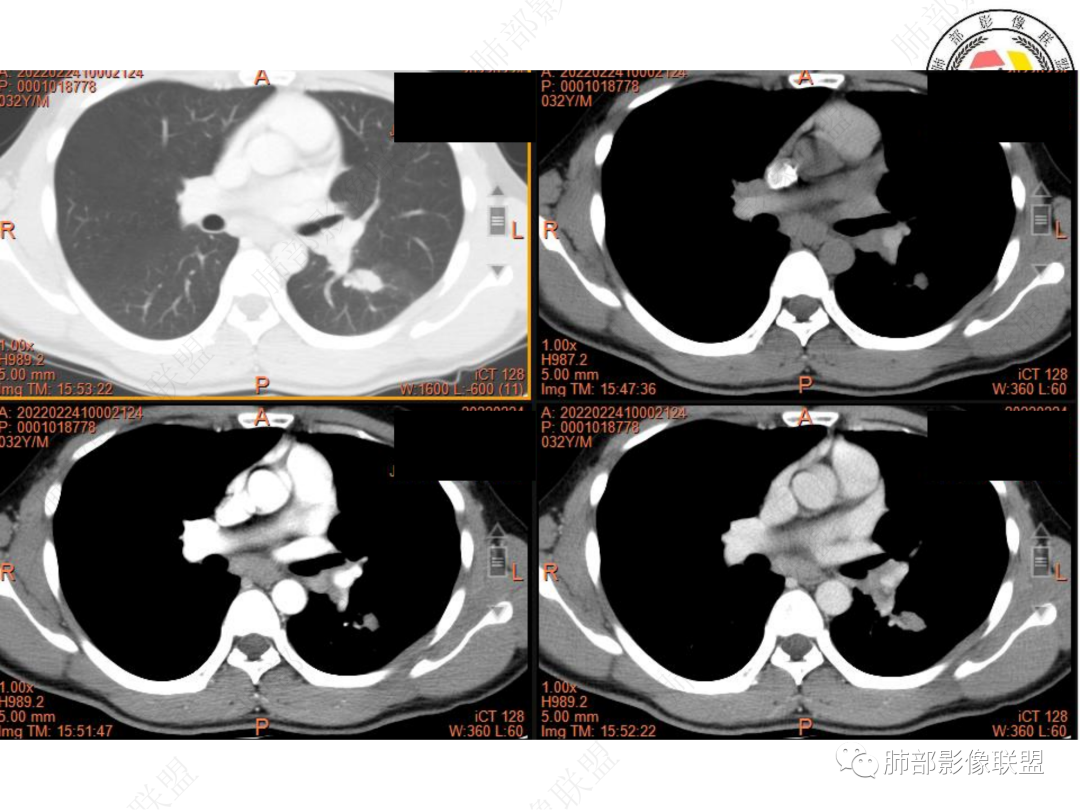

3. CT示左肺下叶背段孤立实性密度结节影,边缘比较清楚光滑,总体呈现膨隆感,未见分叶毛刺,少张力,部分层面病灶边缘呈现较清楚磨玻璃样密度影,并于磨玻璃影病灶内可见多发小空泡,未见钙化或空洞,增强后病灶显示不均匀强化,未见低密度液化区。未见卫星病灶。

左肺门及纵隔内多发淋巴结肿大,大部分淋巴结显示融合,强化不均匀,内见低密度区,疑液化坏死。纵隔内淋巴结部分周围脂肪间隙不清晰。大血管及左肺主支气管未见受侵改变。

5. 此病例青年男性,纵隔淋巴结环形强化,易先入为主诊断结核。但左肺下叶背段病灶密度均匀,强化明显,整体具备膨隆感,缺少炎性病灶的平直征,病灶周围未见卫星灶,应想到新生物可能。纵隔及左肺门肿大淋巴结,虽有部分淋巴结环形强化特点,但是部分淋巴结周围血管脂肪间隙小时、密度增高,强化明显。至此,亦可与结核的环形强化区分开来。尽管患者年轻,但恶性征象出现时,仍应当高度警惕。